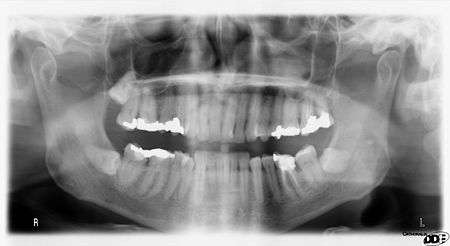

Panoramic radiograph

A dental panoramic radiograph, showing the maxilla and mandible, all the teeth including the "wisdom teeth," the frontal and maxillary sinuses, the nasal cavity and the temporomandibular joint and other near by head and neck anatomy. | |

A panoramic radiograph is a panoramic scanning dental X-ray of the upper and lower jaw. It shows a two-dimensional view of a half-circle from ear to ear. Panoramic radiography is a form of tomography; thus, images of multiple planes are taken to make up the composite panoramic image, where the maxilla and mandible are in the focal trough and the structures that are superficial and deep to the trough are blurred.